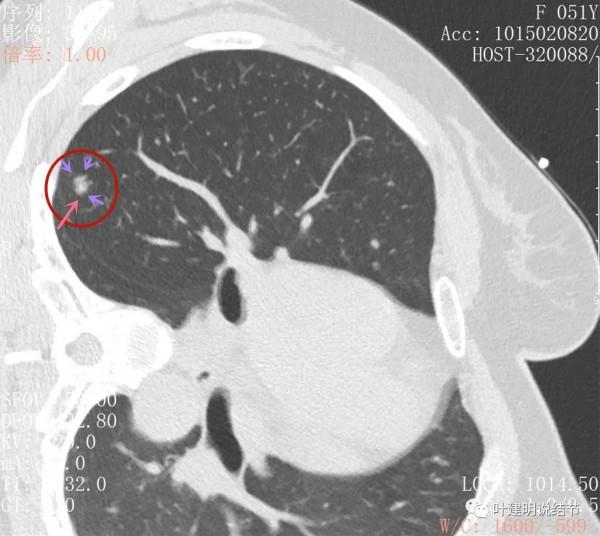

上圖層面居然見到病灶周圍的細毛刺徵(紫色箭頭),有實性成分(粉色箭頭)

密度雜亂,輪廓清楚

實性成分較多,有明顯磨玻璃成分

上圖示微血管有血管彎徵,與病灶界限不清,實性成分佔比較高